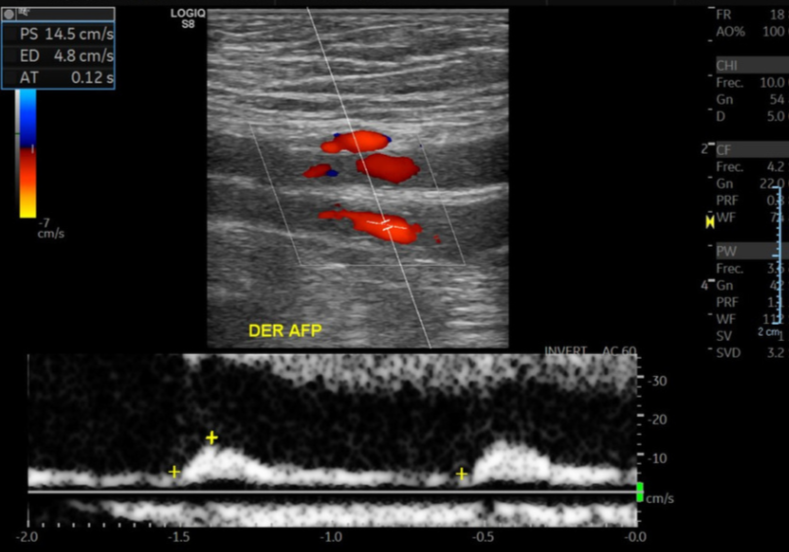

• Curvas arteriales de EEII DER con pérdida de su componente trifásico. Se observan con disminución de VPS habituales y con aumento de su TA.

• En relación AFC y AFP se observa extensa placa de ateroma hipoecoica y heterogénea que genera una estenosis significativa en AFP sobre el 75% con curvas tardus parvus posteriores en AFP.

Hallazgos: Con transductor lineal de alta frecuencia se explora el territorio arterial de la extremidad inferior derecha incluidas las arterias femorales común, femoral superficial, poplítea, tibiales anterior y posterior, peronea y pedia. Placas de ateroma calcificadas en todo territorio arterial de la extremidad inferior, con extensa placa a nivel de la arteria femoral común y profunda generando estenosis de aproximadamente 75% (aumento de velocidad peak sistólico desde 50 cm/s hasta 244 cm/s), con curvas espectrales de morfología parvus tardus en arteria femoral profunda distal a la estenosis. Oclusión completa de la arteria femoral superficial distal, con desarrollo de colaterales que permiten flujo hacia la arteria poplítea. Disminución de velocidad peak sistólico del resto de los vasos de la extremidad inferior, con curvas espectrales de morfología monofásica y parvus tardus. Incidentalmente, se observa aneurisma fusiforme de la aorta abdominal a nivel infrarrenal, en una extensión aproximada de 11.7 cm, con diámetro transverso de 7. 2 cm y anteroposterior de 6.9 cm, con prominente trombo mural que determinan gran disminución del lumen arterial.

Ateromatosis cálcica difusa de la extremidad inferior con extensa placa a nivel de la arteria femoral común y profunda generando estenosis de aproximadamente 75%. Oclusión completa de la arteria femoral superficial distal, con desarrollo de colaterales que permiten flujo hacia la arteria poplítea. Marcada insuficiencia arterial del resto de los vasos de la extremidad inferior. Voluminoso aneurisma fusiforme de la aorta abdominal a nivel infrarrenal, con prominente trombo mural que determinan gran disminución del lumen arterial. Es indispensable evaluación clínica y complementar estudio con AngioTAC de abdomen y pelvis y extremidades inferiores.